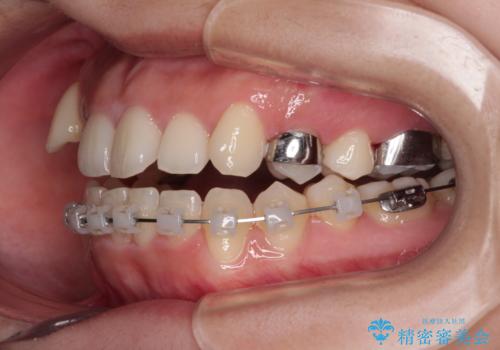

上顎の急速拡大装置を使用して上顎骨を側方に拡大することで上顎歯列を拡大し、下顎歯列も拡大できるようにすることで、歯列を整えることとしました。

歯列矯正では基本的に骨格を改善することはできませんが、急速拡大装置(MARPE)を使用することで上顎骨を側方に拡大させることができ、咬合状態を大きく改善することができます。